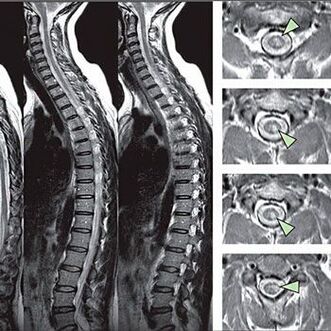

Om tekenen van gevoeligheidsstoornissen te identificeren, worden speciale functionele tests uitgevoerd. De meest informatieve optie van diagnose van instrumentele methoden is de prestaties van een X -Ray. Voor een grondige studie van de wervelkolom worden MRI en CT echter vaak uitgevoerd. In het geval van vermoeden van ziekten van het cardiovasculaire systeem wordt de patiënt aanbevolen om de ECG -procedure te ondergaan.